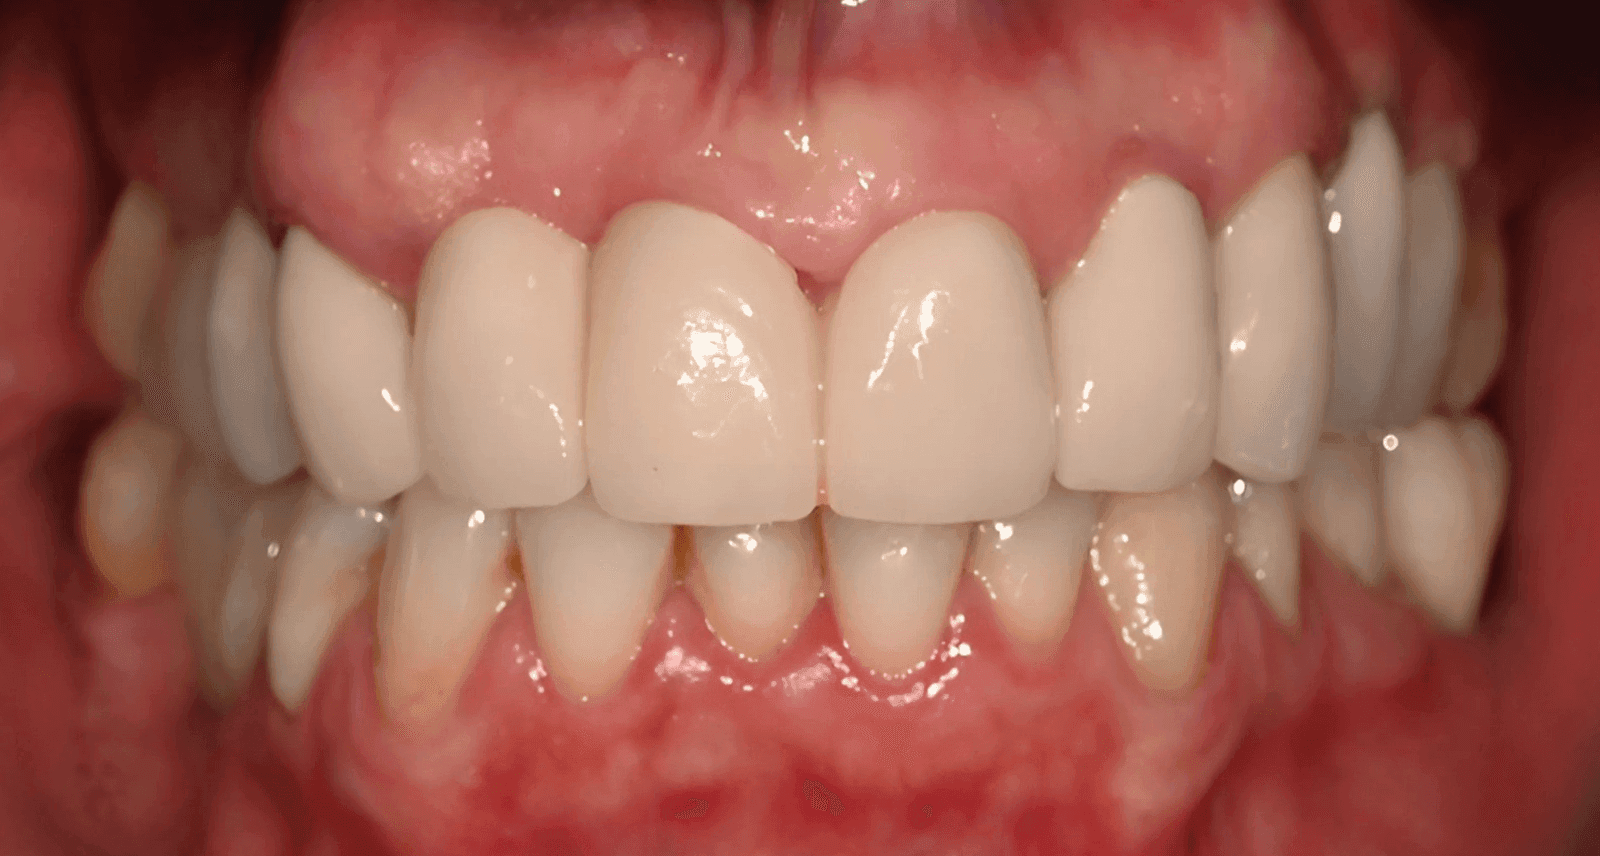

Pacijentkinja je želela da reši problem nedostajućih zuba i unapredi izgled svog osmeha. Zajedno smo prošli kroz proces koji je uključivao detaljnu analizu, ugradnju implantata i izradu krunica. Rezultat? Osmeh koji je oduševio i nju i nas! Evo kako je sve to izgledalo, korak po korak.

Nakon perioda oseointegracije smo pristupili izradi definitivnih krunica od cirkonijum-keramike. Izuzetno smo vodili računa i o krunicama na implantima, koje su urađene na cirkonijum abatmentima.